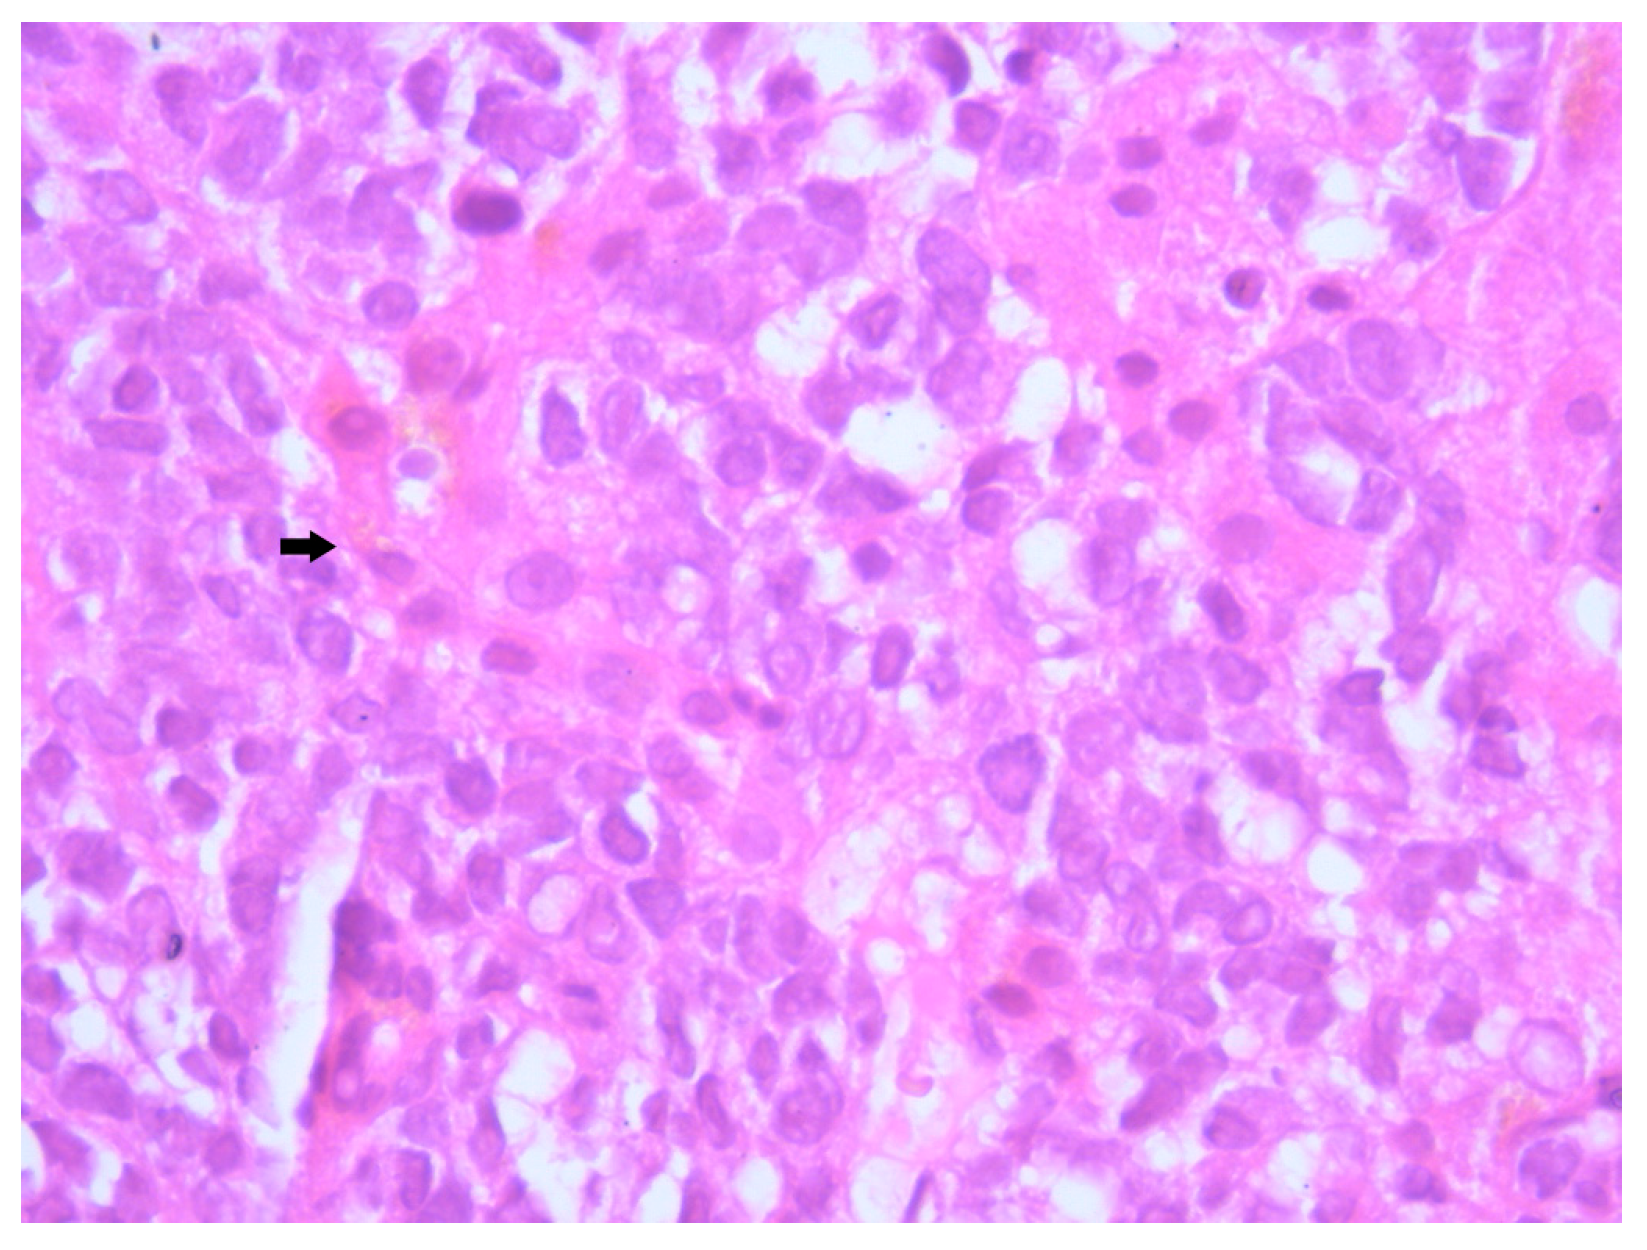

Histopathological examination of the liver biopsy revealed fragments of hepatic parenchyma measuring 10 × 1 mm, with tumoral infiltration by small, round blue cells exhibiting indistinct cytoplasmic borders, scant eosinophilic cytoplasm and round to oval nuclei that were either hyperchromatic or euchromatic, with finely granular chromatin and absent nucleoli. Occasional mitotic figures (4 per 3 HPFs) were identified. The morphology was consistent with a small round blue cell tumor, raising differential diagnostic considerations (Figure 4, Figure 5 and Figure 6). Small round blue cell tumors involving the liver include lymphoma, plasmacytoma, metastatic small-cell lung carcinoma, high-grade neuroendocrine carcinoma, metastatic melanoma, metastatic neuroblastoma and Ewing sarcoma. In contrast to these entities, MCC usually presents with a rapidly growing cutaneous primary tumor, satellite or in-transit metastases and early involvement of regional lymph nodes, as seen in our patient. The combination of morphology (small round blue cells with scant cytoplasm and neuroendocrine features), the presence of a violaceous primary lesion on a sun-exposed site, satellite nodules, marked axillary lymphadenopathy and rapid multiorgan dissemination made MCC the most consistent diagnosis, despite the absence of immunohistochemistry. To clarify the cellular origin and reach a definitive diagnosis, correlation with clinical and paraclinical data, along with immunohistochemical testing (e.g., CK AE1/AE3, CK20, CD56, Chromogranin A, SOX10, CD20, CD3, CD138), would have been essential. The liver biopsy was obtained while the patient was hemodynamically unstable, and within hours he developed biopsy-related hemoperitoneum, shock and multiorgan failure, requiring transfer to the ICU. Due to the rapid clinical deterioration and death shortly afterward, the sample could not be processed for IHC in time, and further invasive tissue sampling was no longer ethically indicated. Nevertheless, the combination of clinical presentation (violaceous cutaneous tumor with satellite nodules), imaging (multiorgan metastases) and morphology of the liver sample (small round blue cells with neuroendocrine features) supported the presumptive diagnosis of metastatic MCC. According to the 8th edition of the American Joint Committee on Cancer (AJCC) staging system for MCC, this case corresponds to Stage IV—cT2N3M1c disease. The T2 classification applies because the primary cutaneous tumor was >2 cm. N3 reflects the presence of clinically evident, macroscopic lymph node involvement together with in-transit metastases (satellite cutaneous nodules). The M1c designation is supported by multiple visceral metastases involving the liver, spleen and suspected bone lesions on CT imaging.

MCC classically exhibits morphological features including small round cells with scant cytoplasm, nuclear molding, and hyperchromatic nuclei with finely granular “salt and pepper” chromatin—features reflective of its neuroendocrine differentiation [13]. In our patient, microscopic examination revealed a proliferation of small, undifferentiated cells with high nuclear-to-cytoplasmic ratio, frequent mitotic figures and dense nuclear chromatin, consistent with these hallmarks. Unfortunately, due to the fulminant clinical deterioration and subsequent death of the patient, immunohistochemical (IHC) profiling could not be completed. Nevertheless, the suggestive histological pattern in combination with the rapid evolution and metastatic behavior strongly supported the diagnosis of MCC. While IHC remains critical for definitive diagnosis, particularly to differentiate MCC from other small round blue cell neoplasms, the clinicopathological context provided sufficient grounds for a diagnosis.

Figure 6. Hematoxylin–Eosin staining, 40× magnification (HE 40×): The neoplastic cells are small, round, with indistinct cellular borders, minimal eosinophilic cytoplasm, and round to oval nuclei that are either hyperchromatic or euchromatic, with homogeneous chromatin, inconspicuous nucleoli, and rare mitotic figures. Arrows indicate representative neoplastic cells with scant cytoplasm and finely granular chromatin.